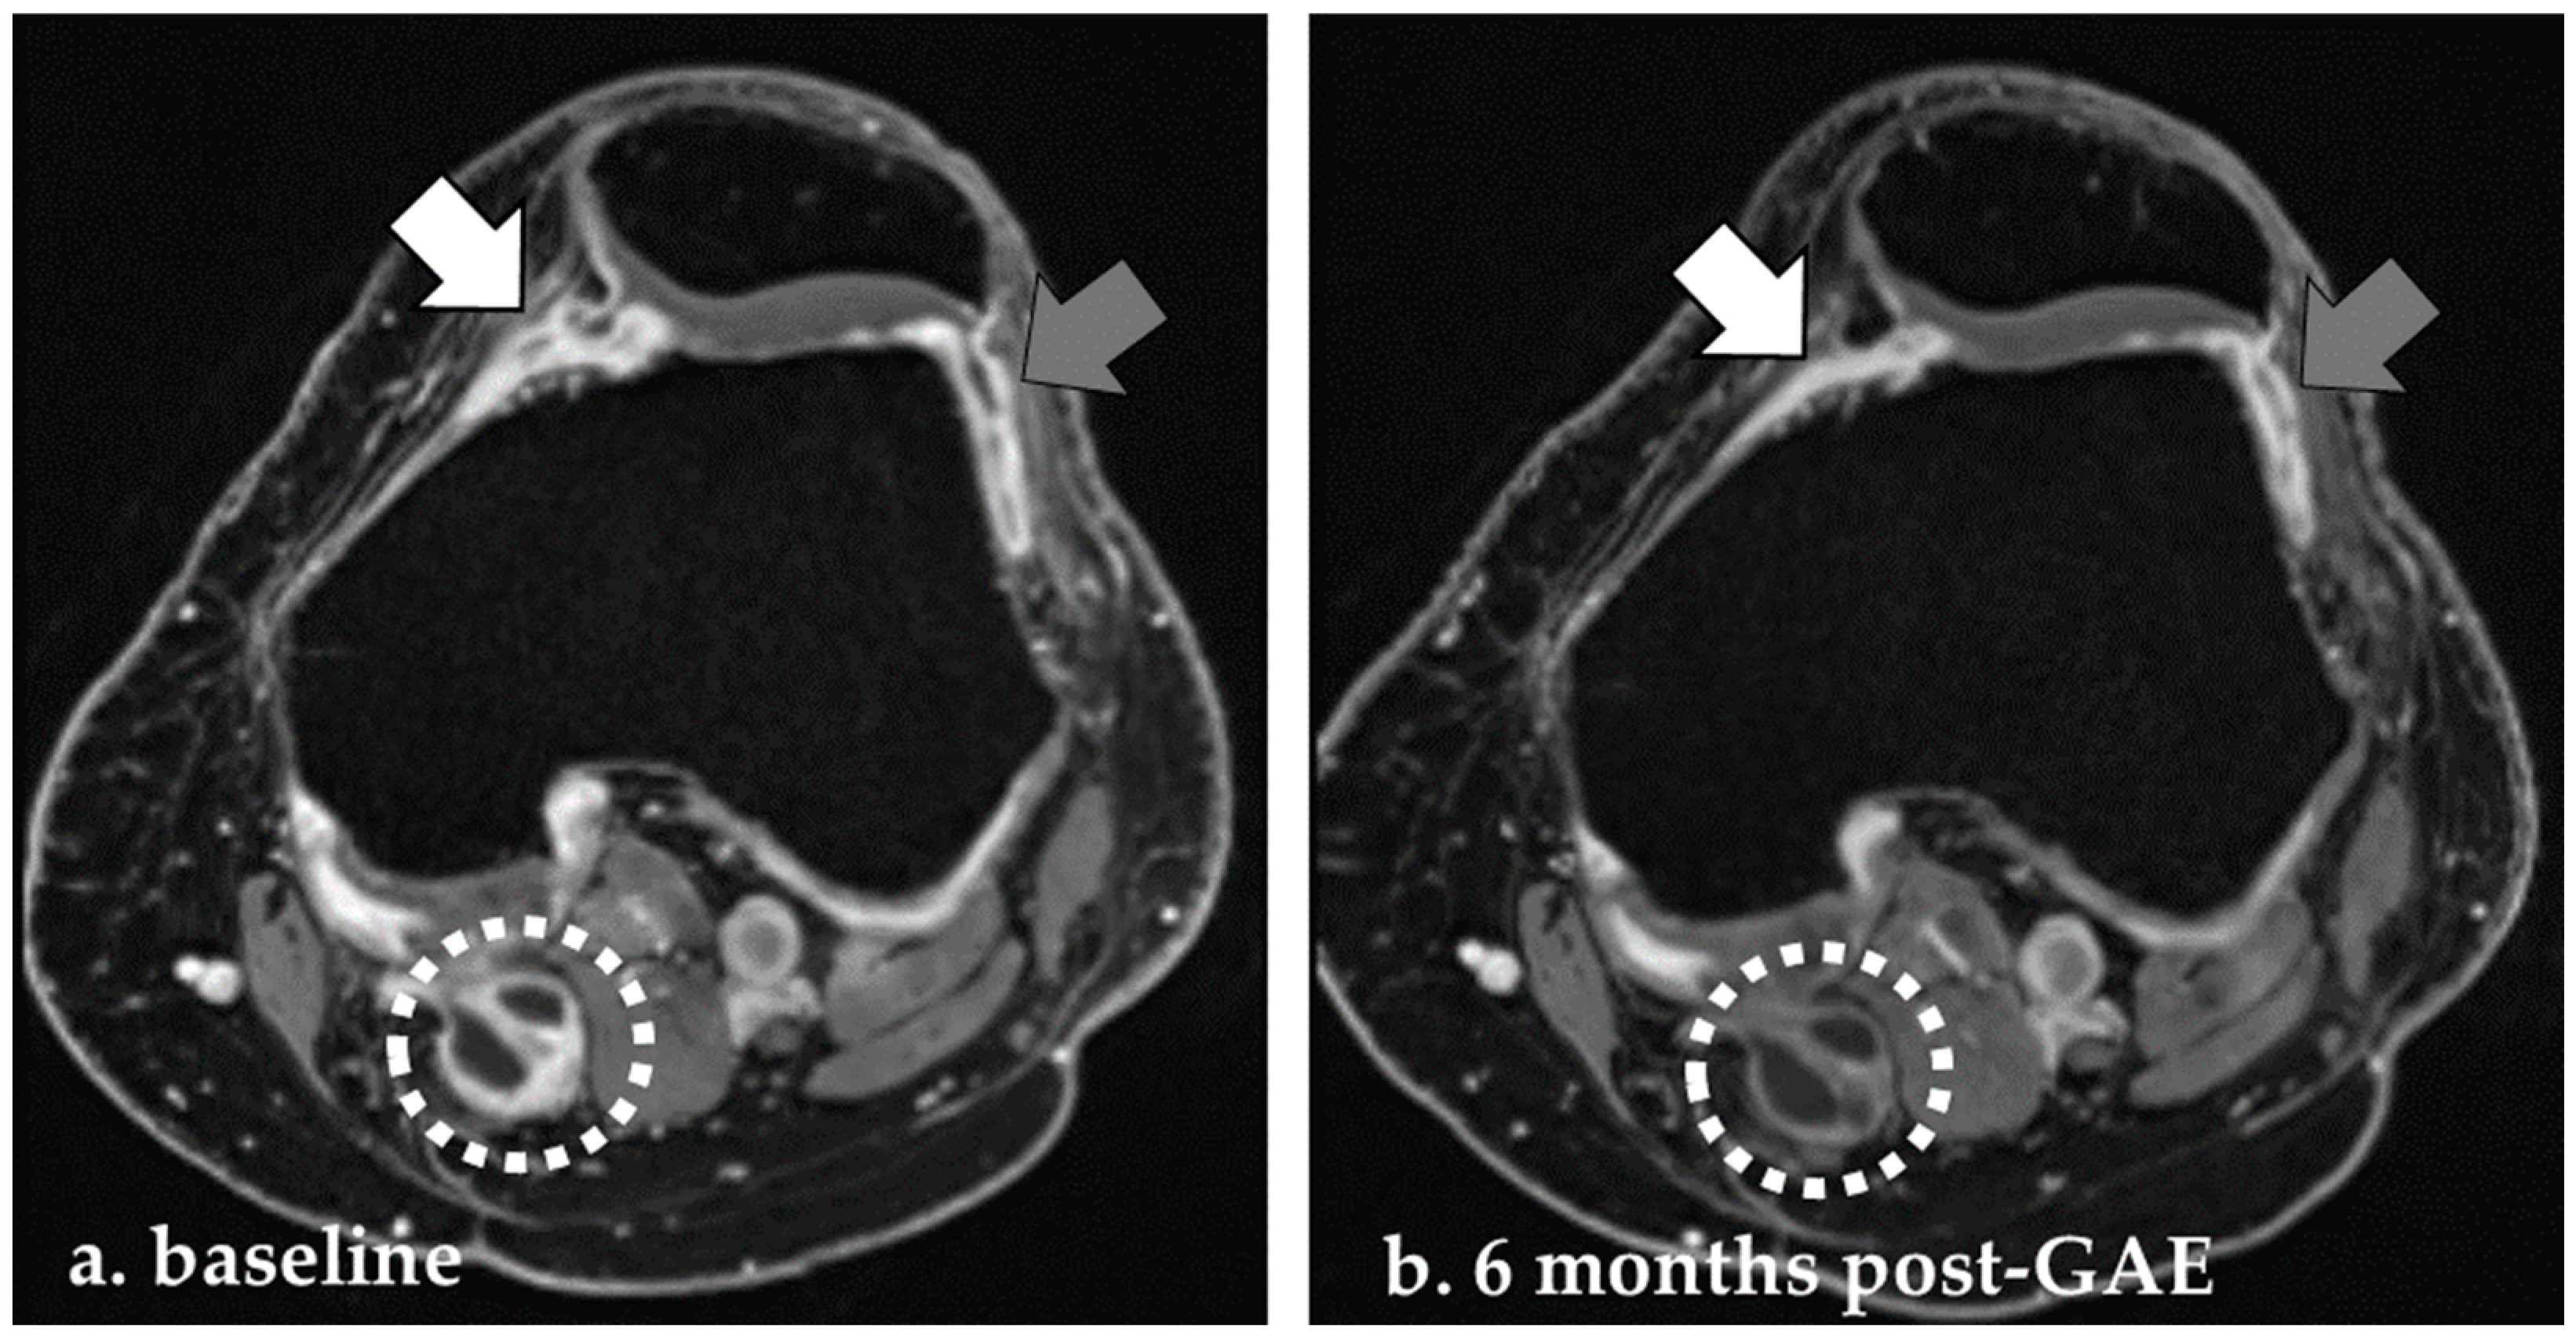

3.2.4. Ischemic Lesions